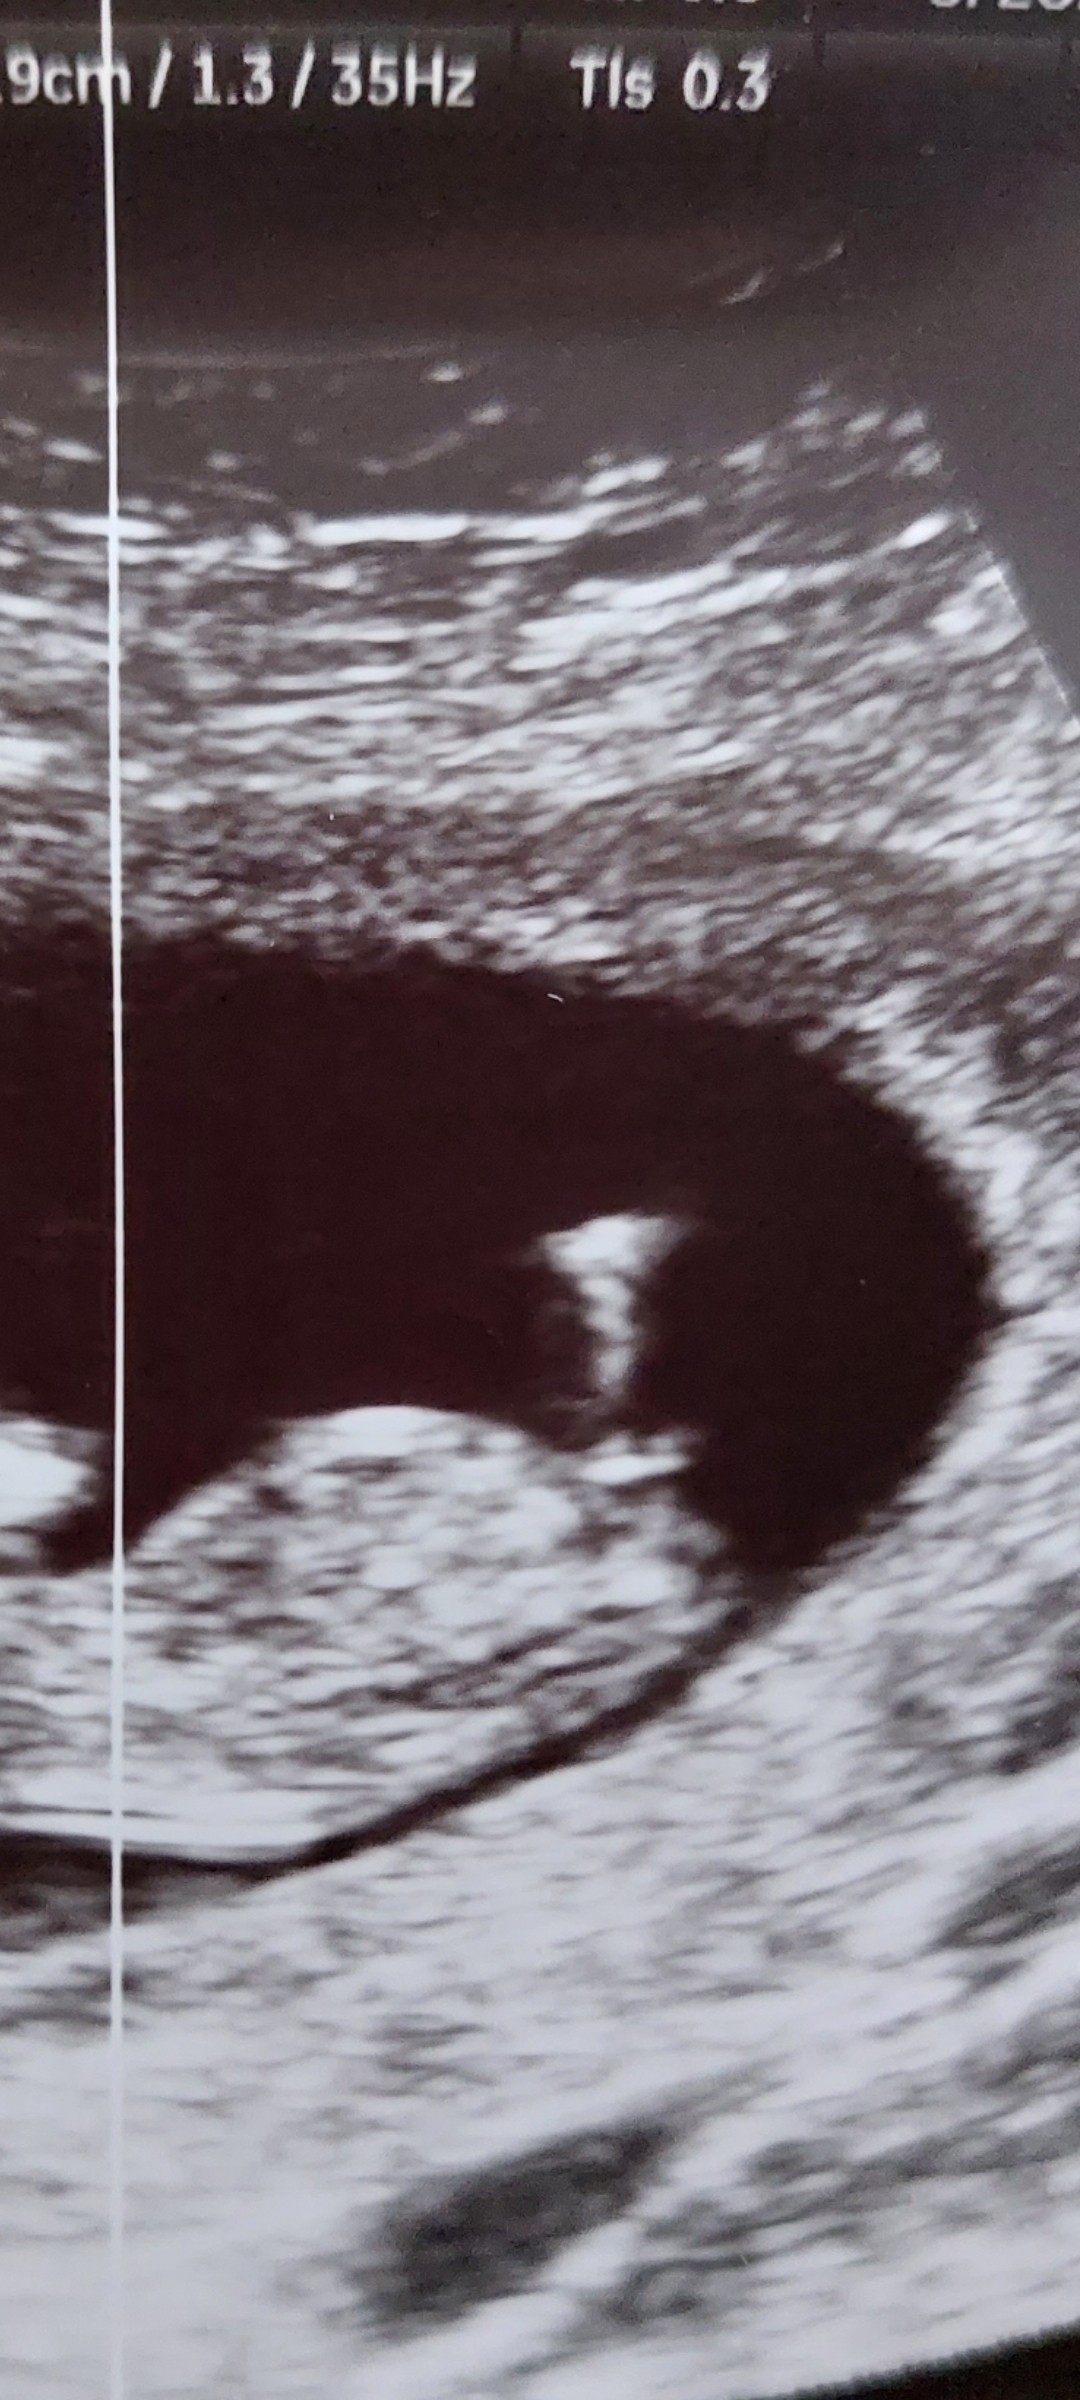

dokładnie o to coś mi chodziłoWydaje mi się że to to![]()

A co powiesz na moje USG dzidzi??dokładnie o to coś mi chodziłona filmiku jest całkiem widoczne i trochę przypomina wyrostek z artykułu u mamyginekolog.

wg mojej internetowej wiedzyA co powiesz na moje USG dzidzi??![]()